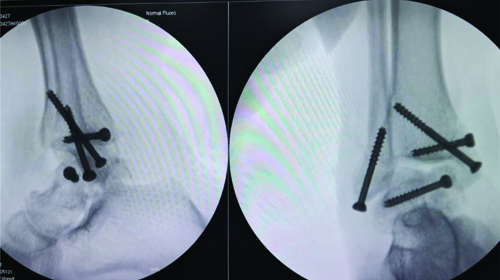

With the patient in the supine position, a medial approach was utilised along the medial malleolar fracture line to expose the talar fracture. The deltoid ligament was protected along with the medial malleolar fragment. The minimally comminuted talar fracture was reduced and fixed with Arbeitsgemeinschaft für Osteosynthesefragen (AO) cancellous lag screws under fluoroscopic guidance. The reduction was optimal due to minimal resorption of the comminuted ends. The medial and lateral malleoli were also fixed with cancellous screws [Table/Fig-3,4].

Intraoperative C-arm picture of fracture fixation.